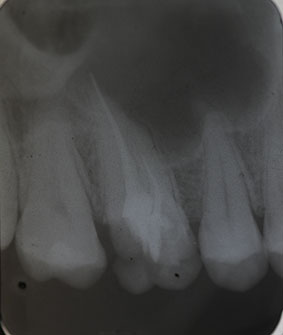

Patient N.M. wünscht eine Drittmeinung, zwischenzeitlich hatte er bereits einen zweiten Zahnarzt konsultiert. Dieser bestätigte eine insuffiziente Wurzelfüllung und vermutete eine Instrumentenfraktur im mb1 (Abb. 1).

Abb. 1: Ausgangsröntgenbild des insuffizient gefüllten Zahnes 16.

Röntgenbefund

Mittels Röntgenaufnahme lässt sich ein frakturiertes Instrument in mb1 vermuten. Des Weiteren scheint es, als sei der distale Wurzelkanal sowie der mb2 nicht abgefüllt worden, was sich zu einem späteren Zeitpunkt der Behandlung bestätigen sollte. Der Patient wurde vom vorbehandelnden Zahnarzt über die Fraktur nicht aufgeklärt.